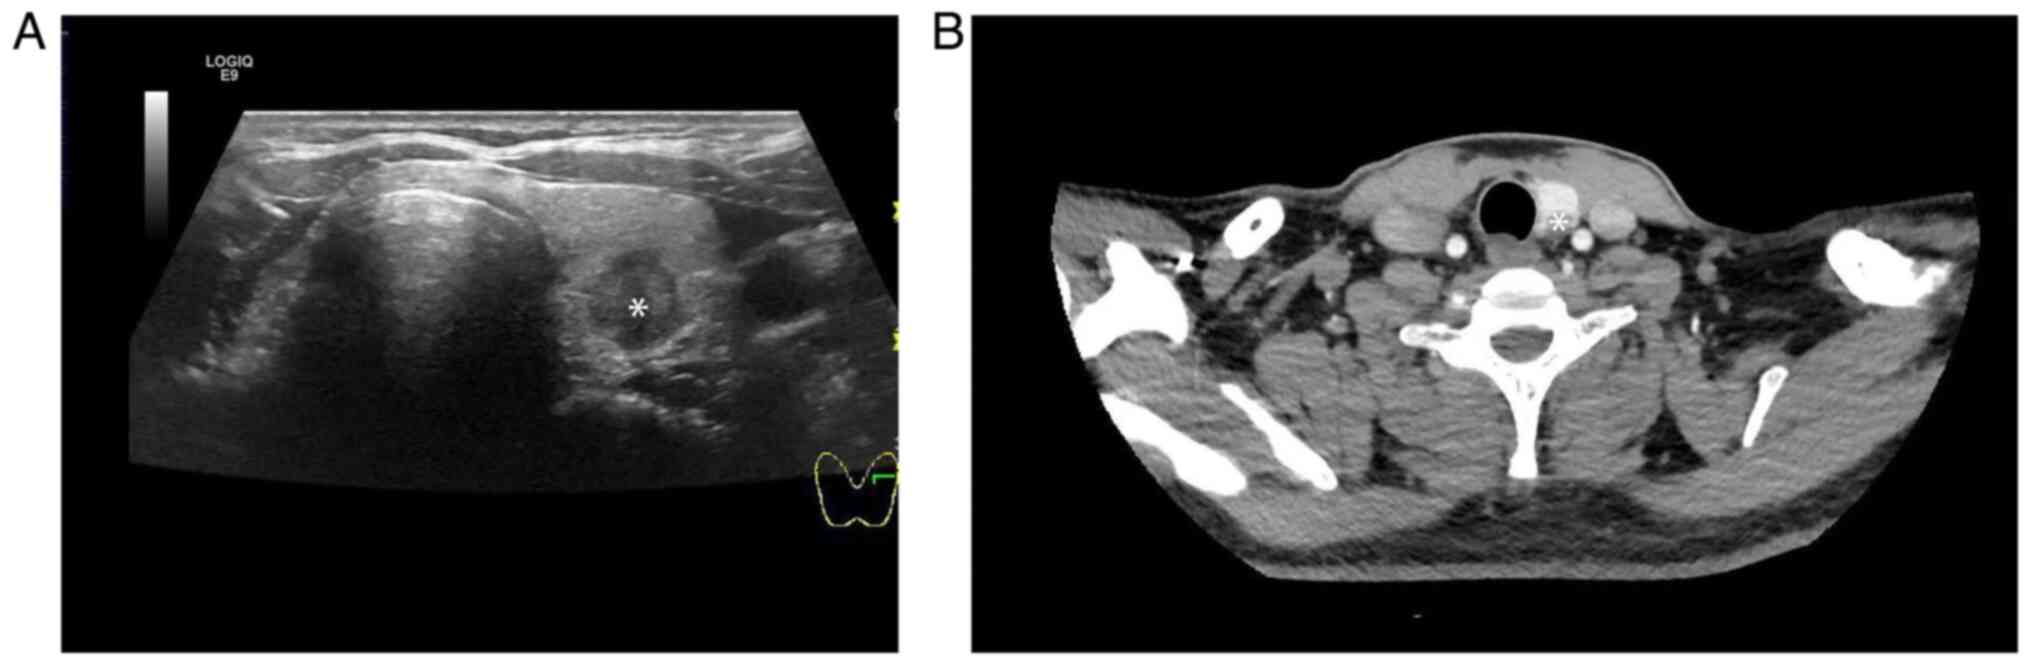

Ultrasound of the neck revealed that the left thyroid lobe contained an irregular, hypoechoic, hypervascular tumor with a long diameter of 1.5 cm (Fig. 1A). Cervical CT imaging showed a thyroid tumor located in the left thyroid (Fig. 1B). The right thyroid lobe could not be visualized in the ultrasound and CT images. The patient underwent fine-needle aspiration cytology. The result showed that the morphology of the cells was spindle shaped (Fig. 2) and MTC was suspected. However, ultrasound and CT showed that no suspicious lymph nodes were apparent.

Figure 1

Ultrasonography and CT images of the thyroid. (A) Ultrasonography revealing a hyperechoic nodule (indicated by an asterisk) in the left lobe without the right thyroid lobe. (B) CT imaging showing a solid nodule (indicated by an asterisk) in the left lobe without the right thyroid lobe. CT, computed tomography.